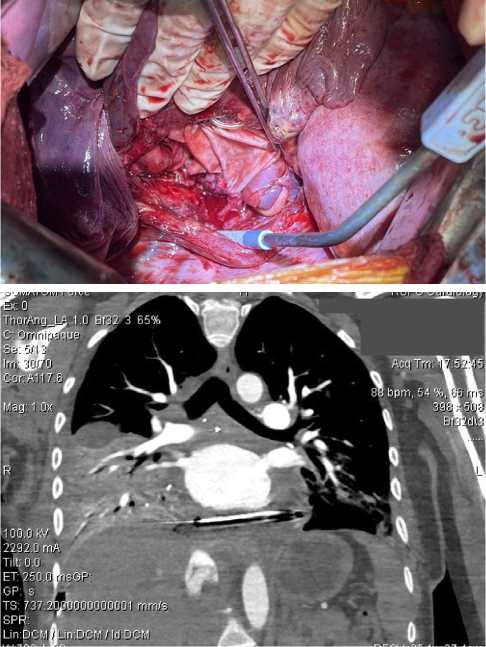

Пациентка Л., 33 года, поступила в онкологическое (торакальное) отделение УЗ «Республиканский-научно практический центр онкологии и медицинской радиологии имении Н.Н. Александрова» (далее — РНПЦ ОМР) с жалобами на повышение артериального давления (САД до 220 мм рт. ст.), давящие боли за грудиной без четкой связи с нагрузкой, ночную периодическую потливость. Из анамнеза заболевания известно, что вышеуказанные жалобы беспокоили в течение 6 мес. Специфическую гипотензивную терапию амбулаторно не принимала. В плане дообследования пациентке выполнено УЗИ сердца, по результатам которого в проекции левого предсердия определялось образование с четкими контурами, размером 84 × 49 мм, сдавливающее левое предсердие, легочные вены. Была заподозрена опухоль висцерального отдела средостения (Лимфома? Бронхогенная/энтерогенная киста?). По результатам компьютерной ангиотомографии органов грудной клетки (КТА ОГК), в заднем отделе средостения определялась опухоль с четкими ровными контурами, с накоплением контрастного вещества с 37 ед.Х до 110 ед.Х, сдавливающая легочную артерию, левое предсердие, с развитием артериальных коллатералей, общим размером 84 × 49 × 71 мм. Консилиумом рентгенологов КТ-картина была описана как опухоль заднего средостения с преимущественным интраперикардиальным распространением (рис. 1, А). Для оценки инвазии опухоли в структуры сердца пациентке была выполнена магнитно-резонансная томография (МРТ), при которой в проекции заднего отдела средостения определялось образование, размером 85 × 78 × 55 мм, с четким ровным наружным контуром, сдавливающее полость левого предсердия, уменьшая его объем. По сигнальным МР-характеристикам структура опухоли изоинтенсивна мышечной ткани.

Рис. 1. Результаты рентгенологических методов исследования: А — КТА-ОГК; Б — ФДГ ПЭТ-КТ; В — Селективная ангиография

Fig. 1. Results of radiological evaluation: A — chest CTA; Б — FDG-PET-CT; B — selective angiography

Для дифференциальной диагностики с лимфопролиферативными заболеваниями, а также для уточнения распространенности опухолевого процесса была выполнена позитронно-эмиссионная томография с фтордезоксиглюкозой (ФДГ ПЭТ-КТ) (рис. 1, Б), по результатам которой в висцеральном отделе средостения определялось гетерогенное солидное образование с четкими контурами, размером до 80 × 53 × 70 мм, содержащее в структуре единичные линейные сосуды. Опухоль диффузно и неравномерно накапливала радиофармпрепарат (SUVmax 2,7-6,1).

При ангиографии установлен источник кровоснабжения опухоли: ветви левой бронхиальной артерии (рис. 1, В). Однако селективная установка микрокатетера оказалась невозможной в связи с выраженной извитостью ветвей бронхиальной артерии, что сделало проведение безопасной эмболизации невозможной.